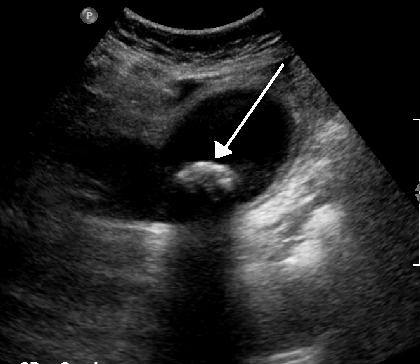

복부초음파에서 발견된 담석 (출처 : 위키미디어)

영상 의학 검사는 복부초음파, 방사성 동위원소 스캔, 복부 전산화 단층 촬영(CT), 복부 자기공명 영상(MRI), 초음파 내시경 등이 있습니다. 영상의학검사로 염증으로 인해 담낭이 부어 있고 주위 장기가 영향을 받아 있는 것을 확인할 수 있습니다. 또한 담낭염을 일으키는 대부분의 원인인 담석을 발견할 수도 있다는 장점이 있습니다.